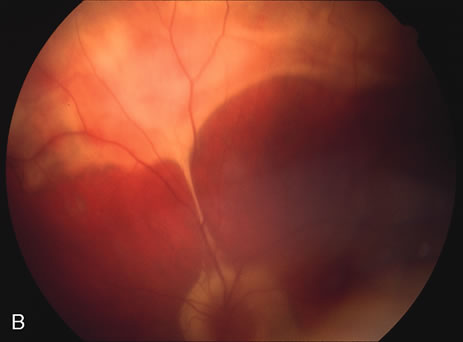

Fundus Findings

In the acute phase, the most common finding is the multiple creamy ovoid yellow-white patches that radiate out from the optic disc and are approximately one half to three fourths disc diameter in size and with indistinct borders. With time these lesions may atrophy and coalesce causing large areas of chorioretinal atrophy. There may be cystoid macular edema and retinal vasculitis as well. Some cases may also develop choroidal neovascularization, epiretinal membranes, macular holes or cataracts (Fig. 19).

Fig. 19. Vitiliginous lesions radiating from the posterior pole to the periphery. Note they are subtle with indistinct edges.